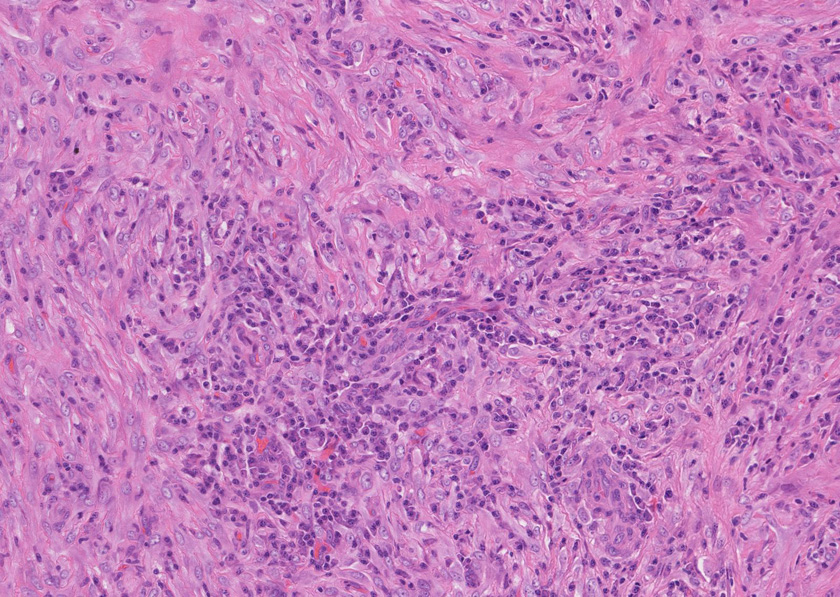

Aには腺房腺管組織に炎症が認められる.

Bの部位では血管中心に形質細胞の密な浸潤像が所見として見られる

Cの部位は増生細胞がSMA陽性となりmyofibroblastの増生病変

膵腺房間質にリンパ球, 形質細胞, 好中球の炎症細胞浸潤が認められる。

線維化組織に類円, 葉巻型淡明な核の紡錘型細胞が増生している。免染SMA陽性。血管周囲に慢性炎症あり。